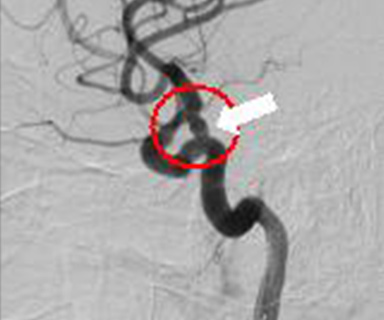

脳動脈瘤

(内頸動脈後交通動脈分岐部)

治療後(コイル塞栓術)

プラチナ製コイル

またクモ膜下出血の原因となる脳動脈瘤や動脈や静脈の異常血管(脳動静脈奇形など)をプラチナ製の針金(コイル)を詰め、血流を遮断して治療することができます。